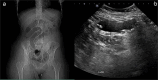

An intragastric balloon is often used as a temporary solution for weight loss. It is endoscopically placed into the stomach and filled with air or saline to encourage fullness and reduce meal intake. A 23-year-old female with a history of a gastric balloon procedure presented to the emergency department with generalized abdominal pain and recurrent vomiting. Initial imaging with ultrasound and computed tomography scans revealed a collapsed migrated gastric balloon causing a small bowel obstruction. Despite initial conservative management, the patient required surgical intervention, which involved laparoscopic exploration, mini laparotomy, and enterotomy to extract the migrated balloon. Postoperatively, the patient had an uneventful recovery and was discharged with a stable condition. This case underscores the importance of considering device-related complications in patients with gastric balloons presenting with gastrointestinal symptoms and highlights the need for prompt imaging and appropriate surgical management. Intragastric balloon migration leading to small bowel obstruction is a rare but serious complication that should be considered in patients presenting with abdominal pain and vomiting following a gastric balloon procedure. Prompt imaging and surgical intervention are crucial for effective management and favorable outcomes.